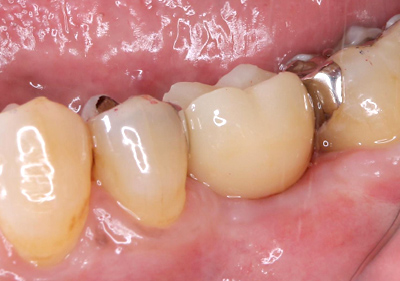

インプラント(骨造成術あり)

費用:50万円

治療期間:12ヶ月

メリット:隣の歯を削らない。歯と同じように噛める。

デメリット:骨、歯肉の状態では外科処置を数回行う場合あり。

治療後![]() |